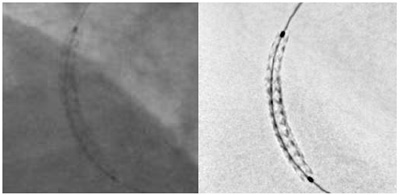

QOL(Quality of life)向上への関心と患者意識が高まる中,これまでの外科手術に比べて侵襲の少ないインターベンション(IVR)は近年増加しており,また昨今では従来開胸・開腹術が必要だった胸部・腹部の大動脈瘤に対するステントグラフト術が可能になるなど,その高度化が加速されている。IVRの普及ならびに高度化に合わせて,血管撮影装置にはステントなどのデバイスと病変部をともにクリアに描出することが求められているが,逆にステントの改良でその薄さが一段と増す中,視認性低下が課題となっていた。今回発売する新製品3機種では,撮影中にステントのみを抽出してクリアに描出可能な「StentViz(ステントビズ)」を搭載,ステントの両端にあるマーカーボールのみならず,ガイドワイヤーの動きも的確に認識して高精細に描出,留置時の正確性を格段に向上している(下図参照)。

従来のステント画像(左)と「StentViz」を使用したステント画像(右)